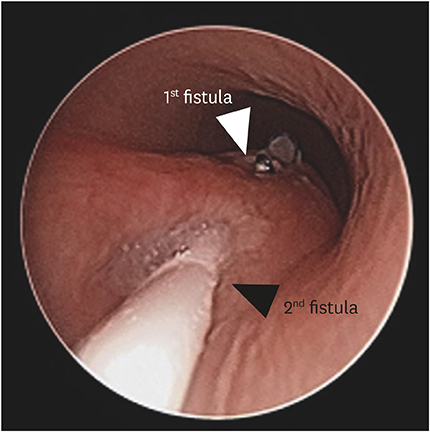

Two months later, on the 124

th day of life, the baby underwent esophagogram to reassure the existence and location of the second H-type fistula. Identifying the fistula at T2 level, a second operation was scheduled on the 146

th day of life. A rigid bronchoscopy was performed to confirm the second H-type fistula just before the operation. Fistula opening was finally visible at 2 cm above the previously repaired site, and a Fogarty catheter was inserted through the opening (

Fig. 4). The lesion was accessed through right cervical incision, and the fistula was located just below the clavicular level. The second fistula was divided and closed with non-absorbable fine sutures. The baby was fed via orogastric tube for two weeks, and oral feeding was tried. The baby was discharged on postoperative day 27 due to transient recurrent laryngeal nerve palsy. He suffered from vocal cord palsy and hypopharyngeal motility disorder but symptoms alleviated gradually and disappeared when the baby was one year old.

Fig. 4 Rigid bronchoscopy just before 2nd operation showing a fistula opening. Suture material was visible at 2–3 cm below the catheter (white and black arrowheads).